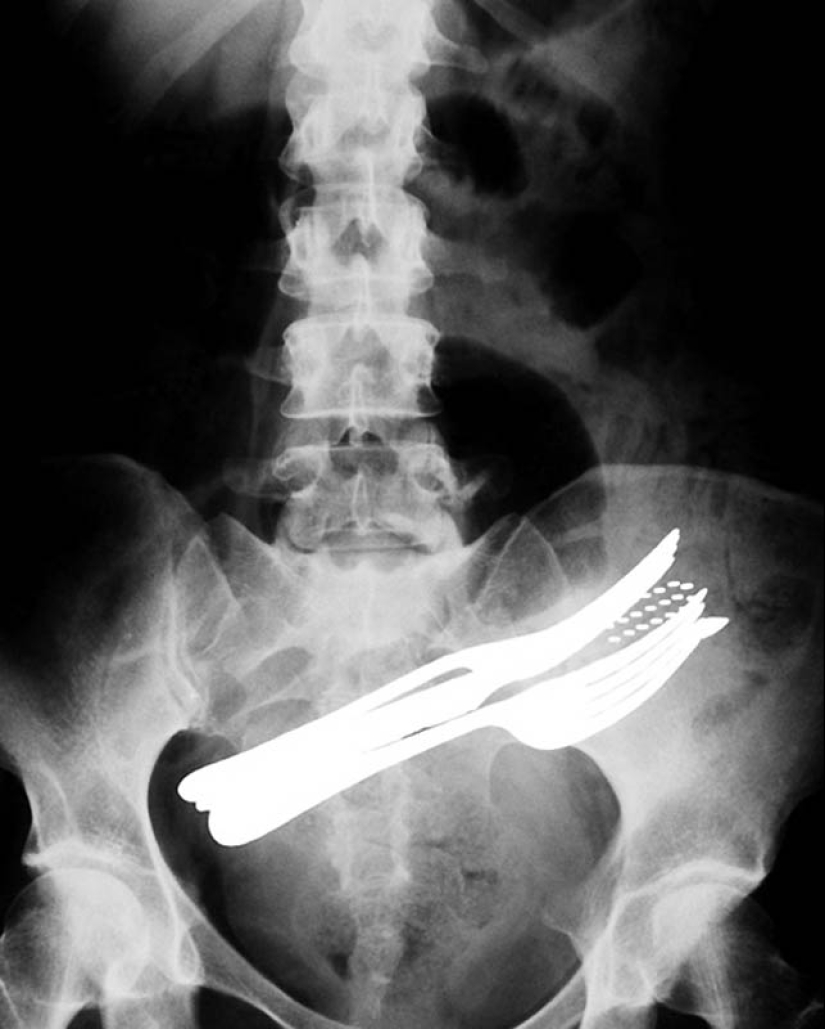

2. El estómago de un paciente que se ha tragado dos tenedores, un bolígrafo y un cepillo de dientes.